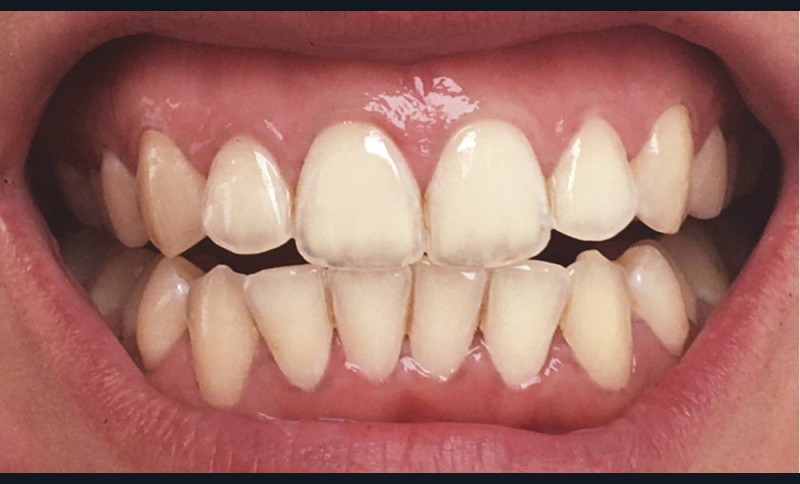

Les modifications hormonales à mettre en relation avec l’hygiène bucco-dentaire, les paramètres socio-économiques, l’âge précoce de la grossesse ainsi que l’augmentation du grignotage pourraient augmenter la prévalence des caries dentaires chez la femme enceinte. Ces patientes sont régulièrement sujettes à des envies multipliant le nombre de prises alimentaires souvent très riches en sucre. Ces apports sucrés, associés à la baisse du pH salivaire lors de la grossesse, entraînent un déséquilibre du cycle déminéralisation et de reminéralisation. Le risque carieux peut être augmenté, ainsi que la susceptibilité à l’érosion dentaire accrue par les vomissements et/ou les reflux gastro-œsophagiens [2]. L’action hormonale peut également avoir des répercussions sur les tissus parodontaux. La gingivite gravidique observée sur plus d’une femme enceinte sur deux, constitue une réponse inflammatoire de la gencive exacerbée par la présence de plaque bactérienne, et favorisée par l’augmentation des taux d’œstrogène et de progestérone [3] (fig. 1). 5 % des futures mères développeront un épulis, dont l’étiologie reste méconnue (fig. 2) [4].

Lorsque l’on consulte les sites internet, il n’existe pas de consensus quant à la technique de son utilisation. Il est généralement conseillé de frotter du citron directement sur les dents (fig. 4), ou de tremper sa brosse à dents dans du jus de citron pur et d’effectuer son brossage. Certains « tutoriels » préconisent d’utiliser ce jus ou de l’eau citronnée comme bains de bouche ! Toutes ces stratégies pour « blanchir » les dents font appel à l’acide citrique contenu dans le citron. Cet acide est l’un des composants les plus présents dans les sodas et autres boissons acides. Si les consommateurs connaissent l’effet néfaste de ces boissons sur leurs dents, ils ne font malheureusement pas le rapprochement avec le citron, un fruit, forcément bon pour la santé. Malgré un grand nombre d’études démontrant les effets nocifs érosifs du citron sur les dents définitives comme sur les dents temporaires, ces pratiques continuent à être couramment utilisées [11].

Le processus d’érosion peut être divisé en deux étapes. La première est une déminéralisation partielle. À ce stade, une reminéralisation reste possible car de l’émail déminéralisé subsiste et des ions, calciums, phosphates ou du fluor, peuvent encore s’y fixer. Quand l’utilisation d’un acide devient trop fréquente par rapport aux processus de reminéralisation, les couches superficielles d’émail fragilisées à l’occasion de la première étape sont éliminées. La perte de substance est alors irréversible (fig. 5). Après la perte de l’émail, celle de la dentine sera plus rapide du fait de sa moindre minéralisation [12]. Ces lésions peuvent entraîner des sensibilités difficiles à éradiquer et créer un déficit esthétique, à l’opposé de l’effet recherché initialement. Les effets déminéralisants de l’acide citrique, rendraient la dent plus sensible aux lésions d’abrasion et d’attrition, augmentant d’autant plus la perte de substance [14].

Le biofilm qui se reforme en quelques minutes après le brossage, protège contre l’érosion en agissant comme une barrière de diffusion ou une membrane à perméabilité sélective limitant le contact direct entre et la surface de la dent et les acides [13]. L’action de frotter du citron ou d’en imbiber sa brosse à dents réduit ou supprime l’épaisseur de la pellicule, compromettant ainsi ses propriétés protectrices. Un brossage réalisé juste avant l’application d’acide citrique est donc délétère. Il en est de même immédiatement après, car cela va éliminer l’émail préalablement déminéralisé par le citron.

Des études [15, 16] de l’état de santé bucco-dentaire tendent à montrer que la prévalence de l’érosion dentaire a augmenté dans les pays industrialisés, alors que celle des lésions carieuses a diminué de façon constante au cours de ces quarante dernières années. Ces érosions, que nous diagnostiquons de plus en plus souvent chez nos jeunes patients, pourraient devenir un problème de santé publique.